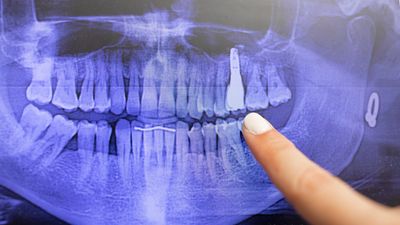

An OPG (Orthopantomogram) is a digital panoramic X-ray of the lower face that displays all the teeth of the upper and lower jaw, on a single film. It provides a broad view of the mouth, including the jaws, teeth, temporomandibular joints (TMJ), nasal area, and sinuses.

OPG is non-invasive, quick, and provides a comprehensive image for diagnosis. It is commonly done to: